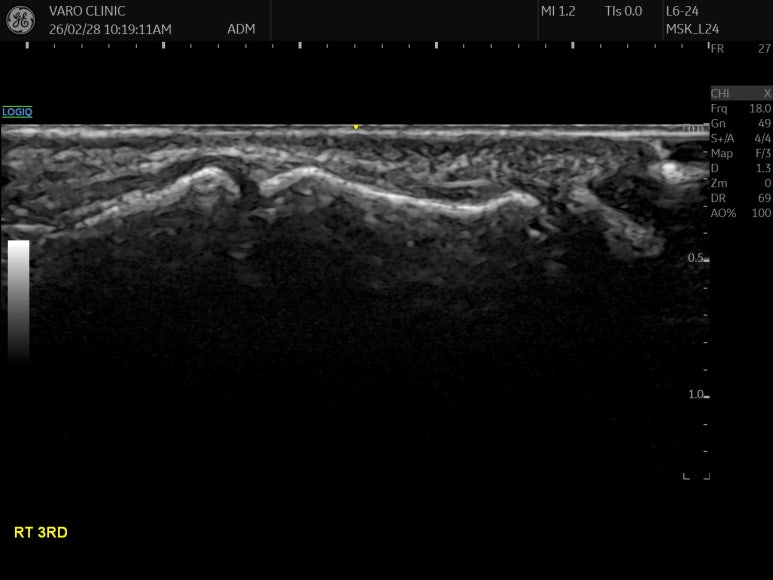

현대 한의학에서는

침 놓는 혈자리,

즉, 경혈을

눈으로만 보는 게 아니고요.

경혈 정밀 초음파를 함께 봅니다.

원래 표준 경혈 초음파상

뼈 표면(골 피질, Cortex)이

연결되어 보여야 하는데요.

Step-off sign